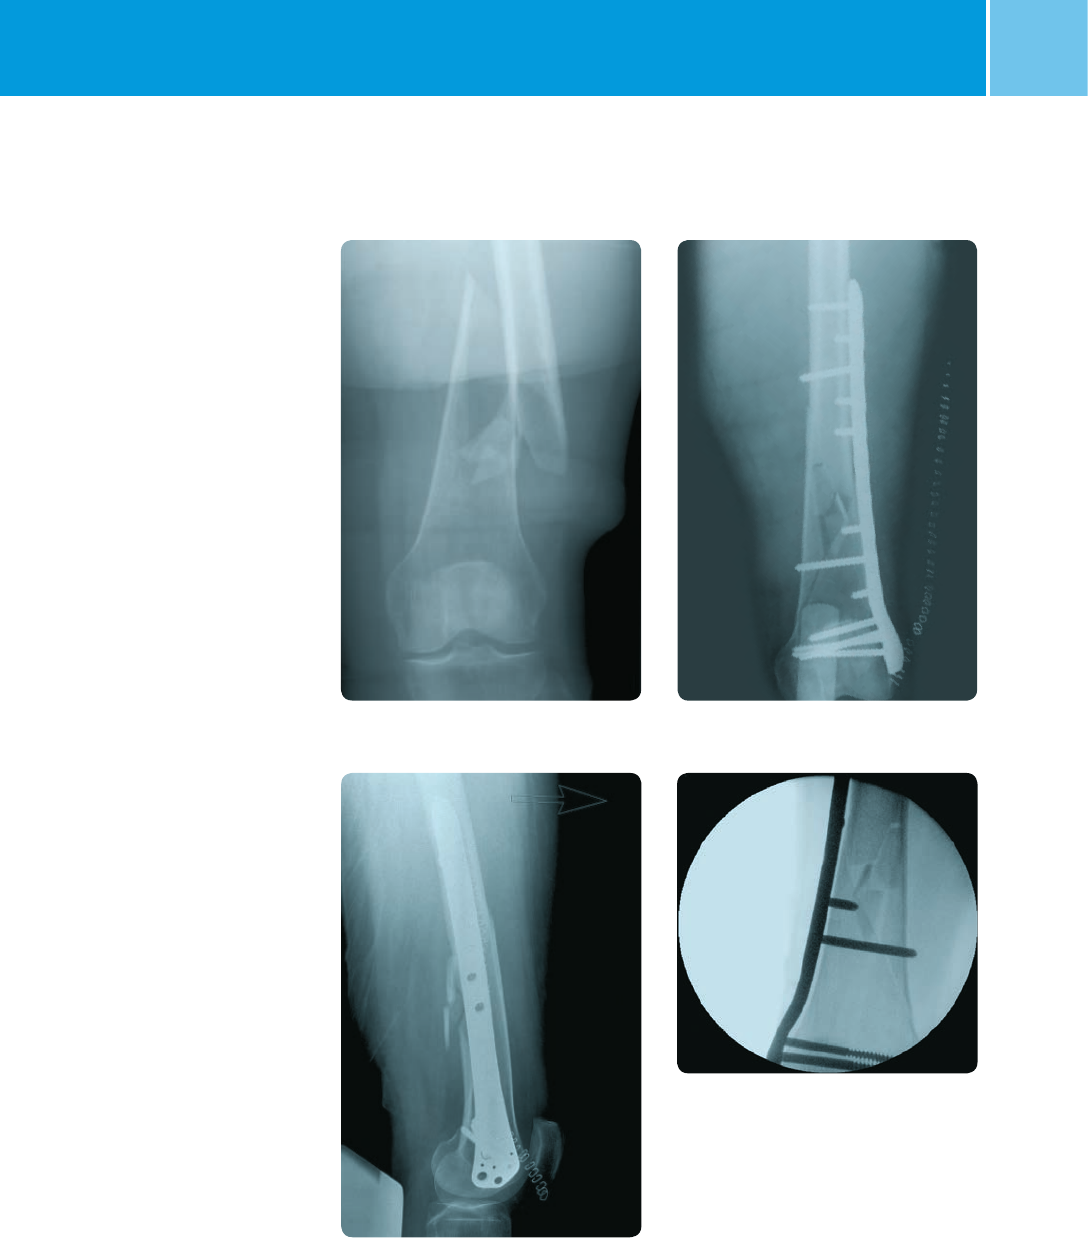

AP view preoperative AP view postoperative

Lateral view postoperative

Lateral view showing ‘non contact’

of the plate

Sample Cases

Case 1: Extra-articular fracture